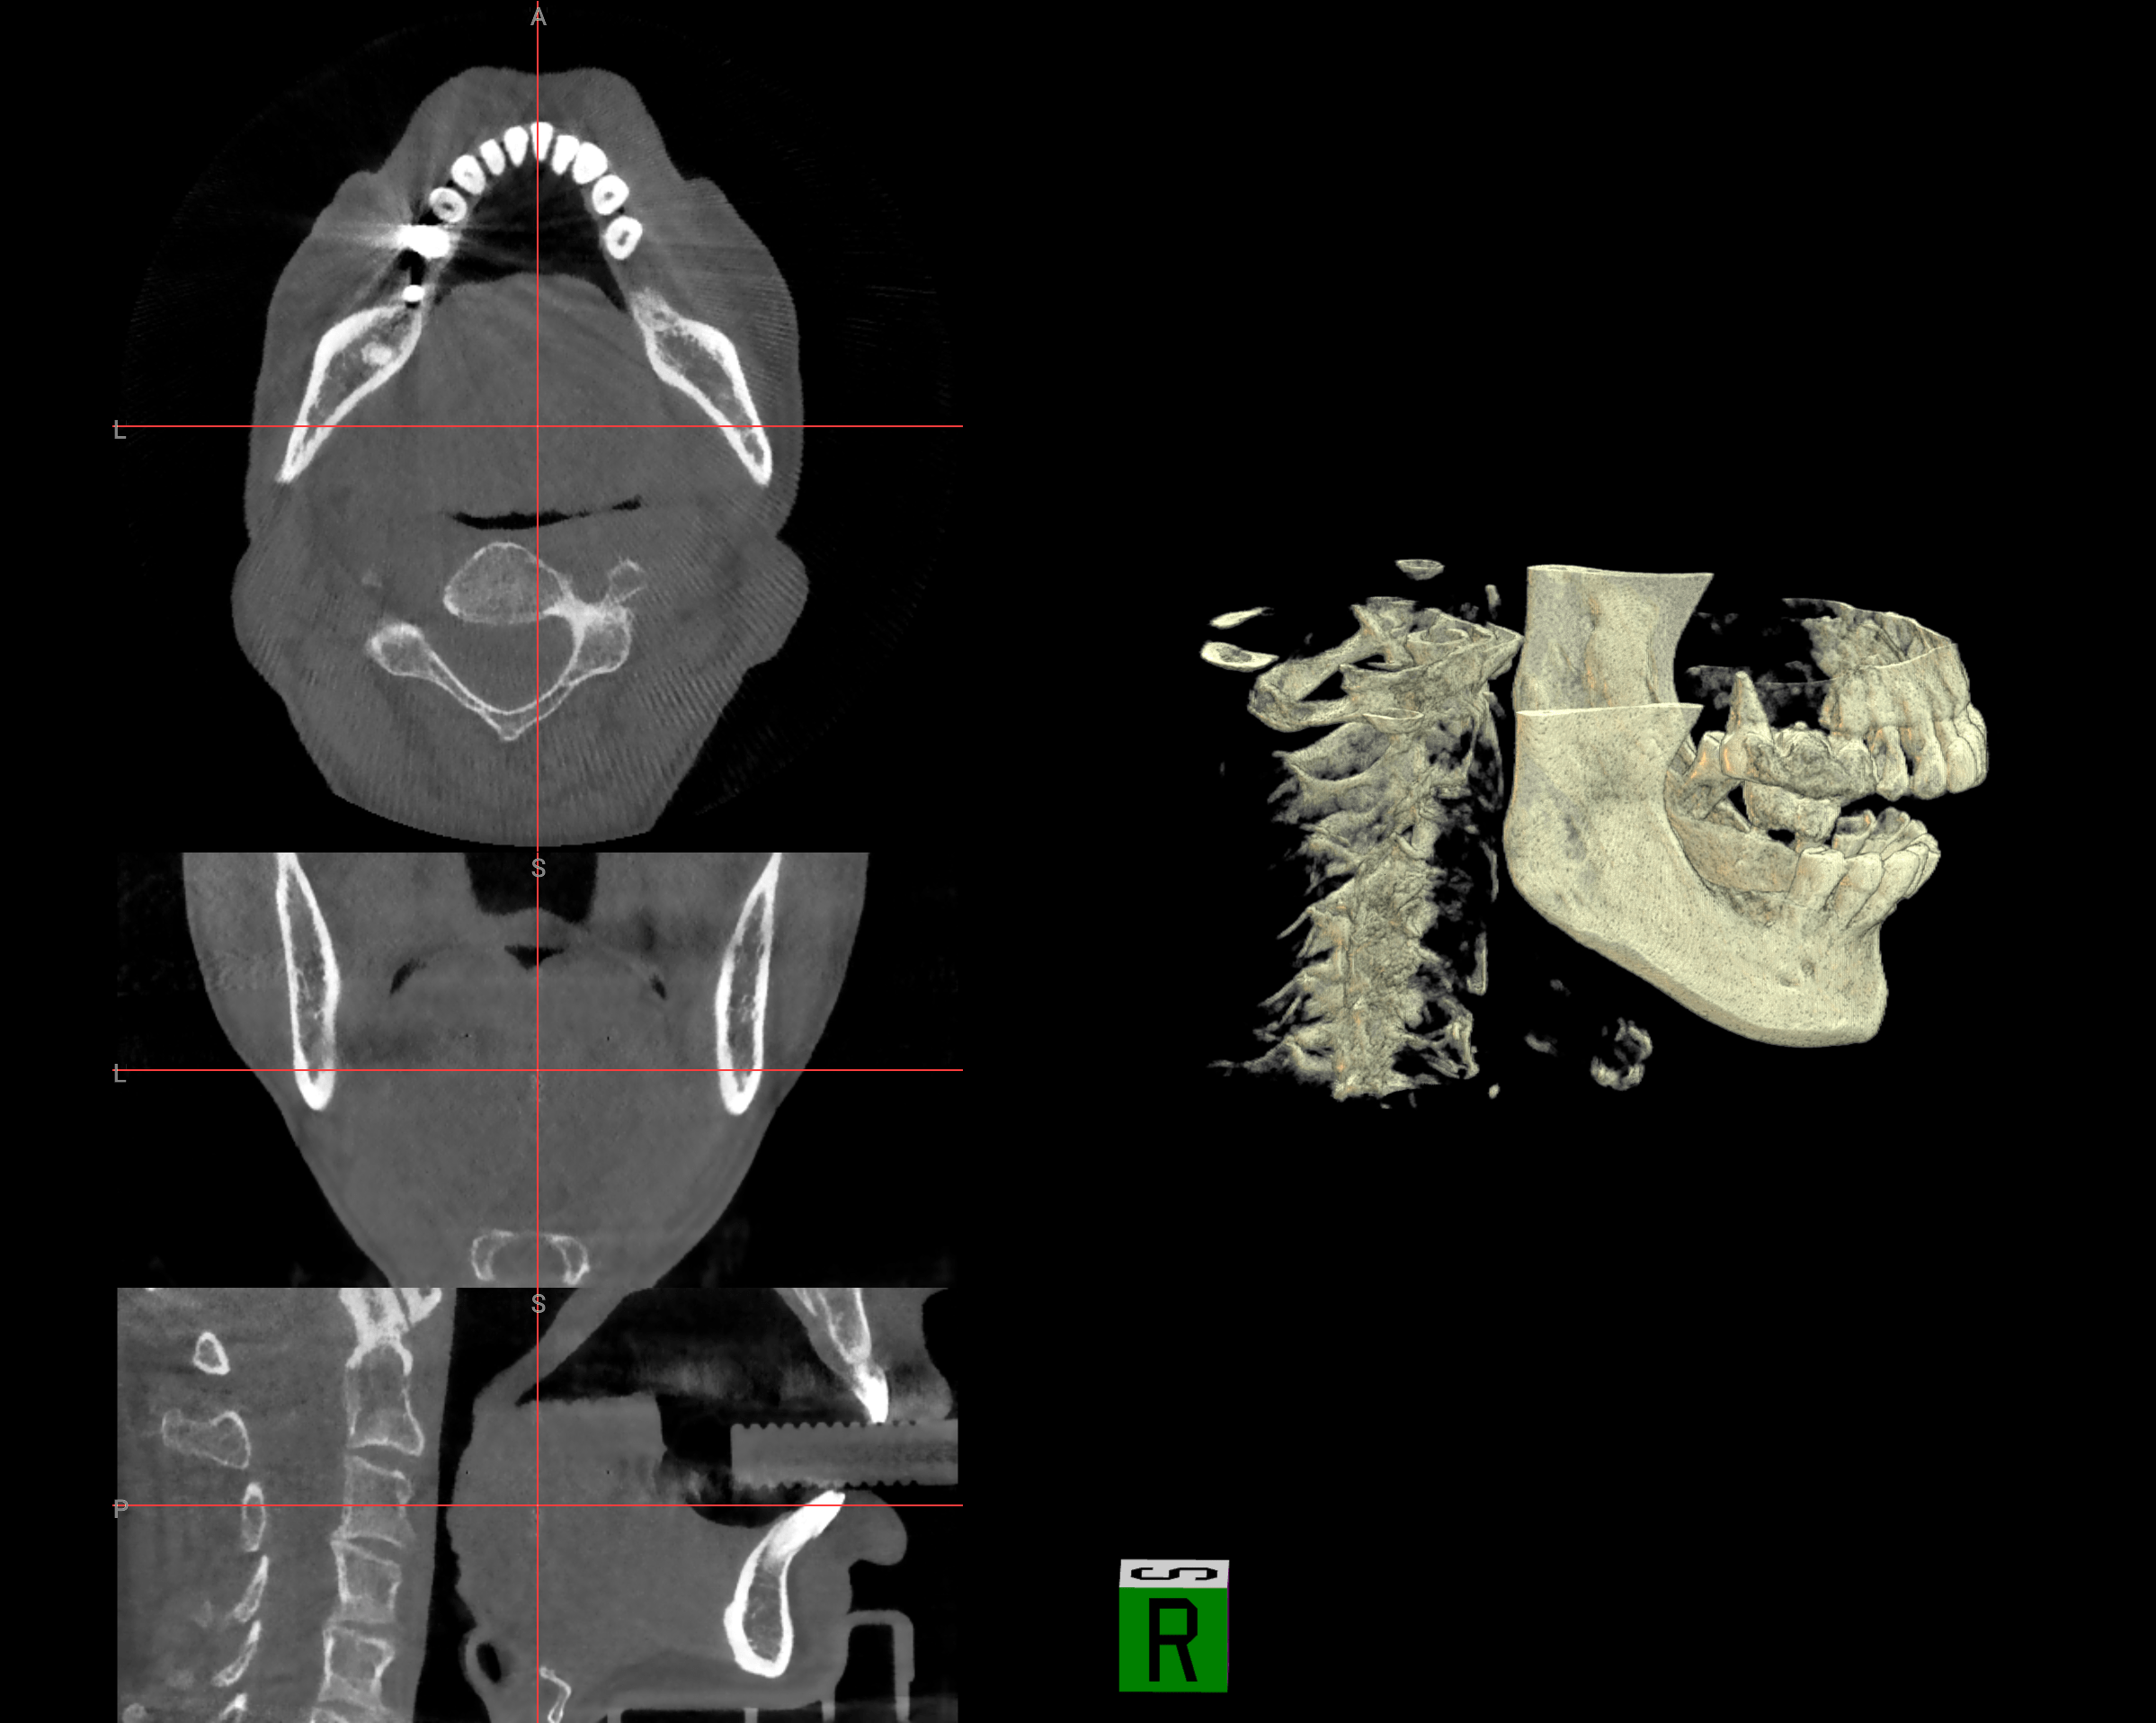

Our multi‑modal AI system includes: CBCT Analyzer & Radious Engine for 3D perception and semantic segmentation; CSI Engine & OLLM (Oral Large Language Model) for cognitive reasoning across 300+ diseases; and an Intelligent Orchestration Layer that delivers findings through conversational interfaces, structured reports, and surgical guide exports.

Advanced conversational interface for clinicians to interact with CBCT scans using natural language. Saves 30-45 minutes per complex case with instant medico-legal reports.